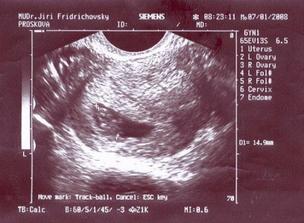

7.1. jsem byla na UTZ a poprvé jsem viděla miminko. Dle poslední MS bych měla být v 10.týdnu, ale dle velikosti spíš na začátku 9.týdne, ale prý se to ještě upřesní. Mám přijít 17.1. ... a dostanu průkazku :o)